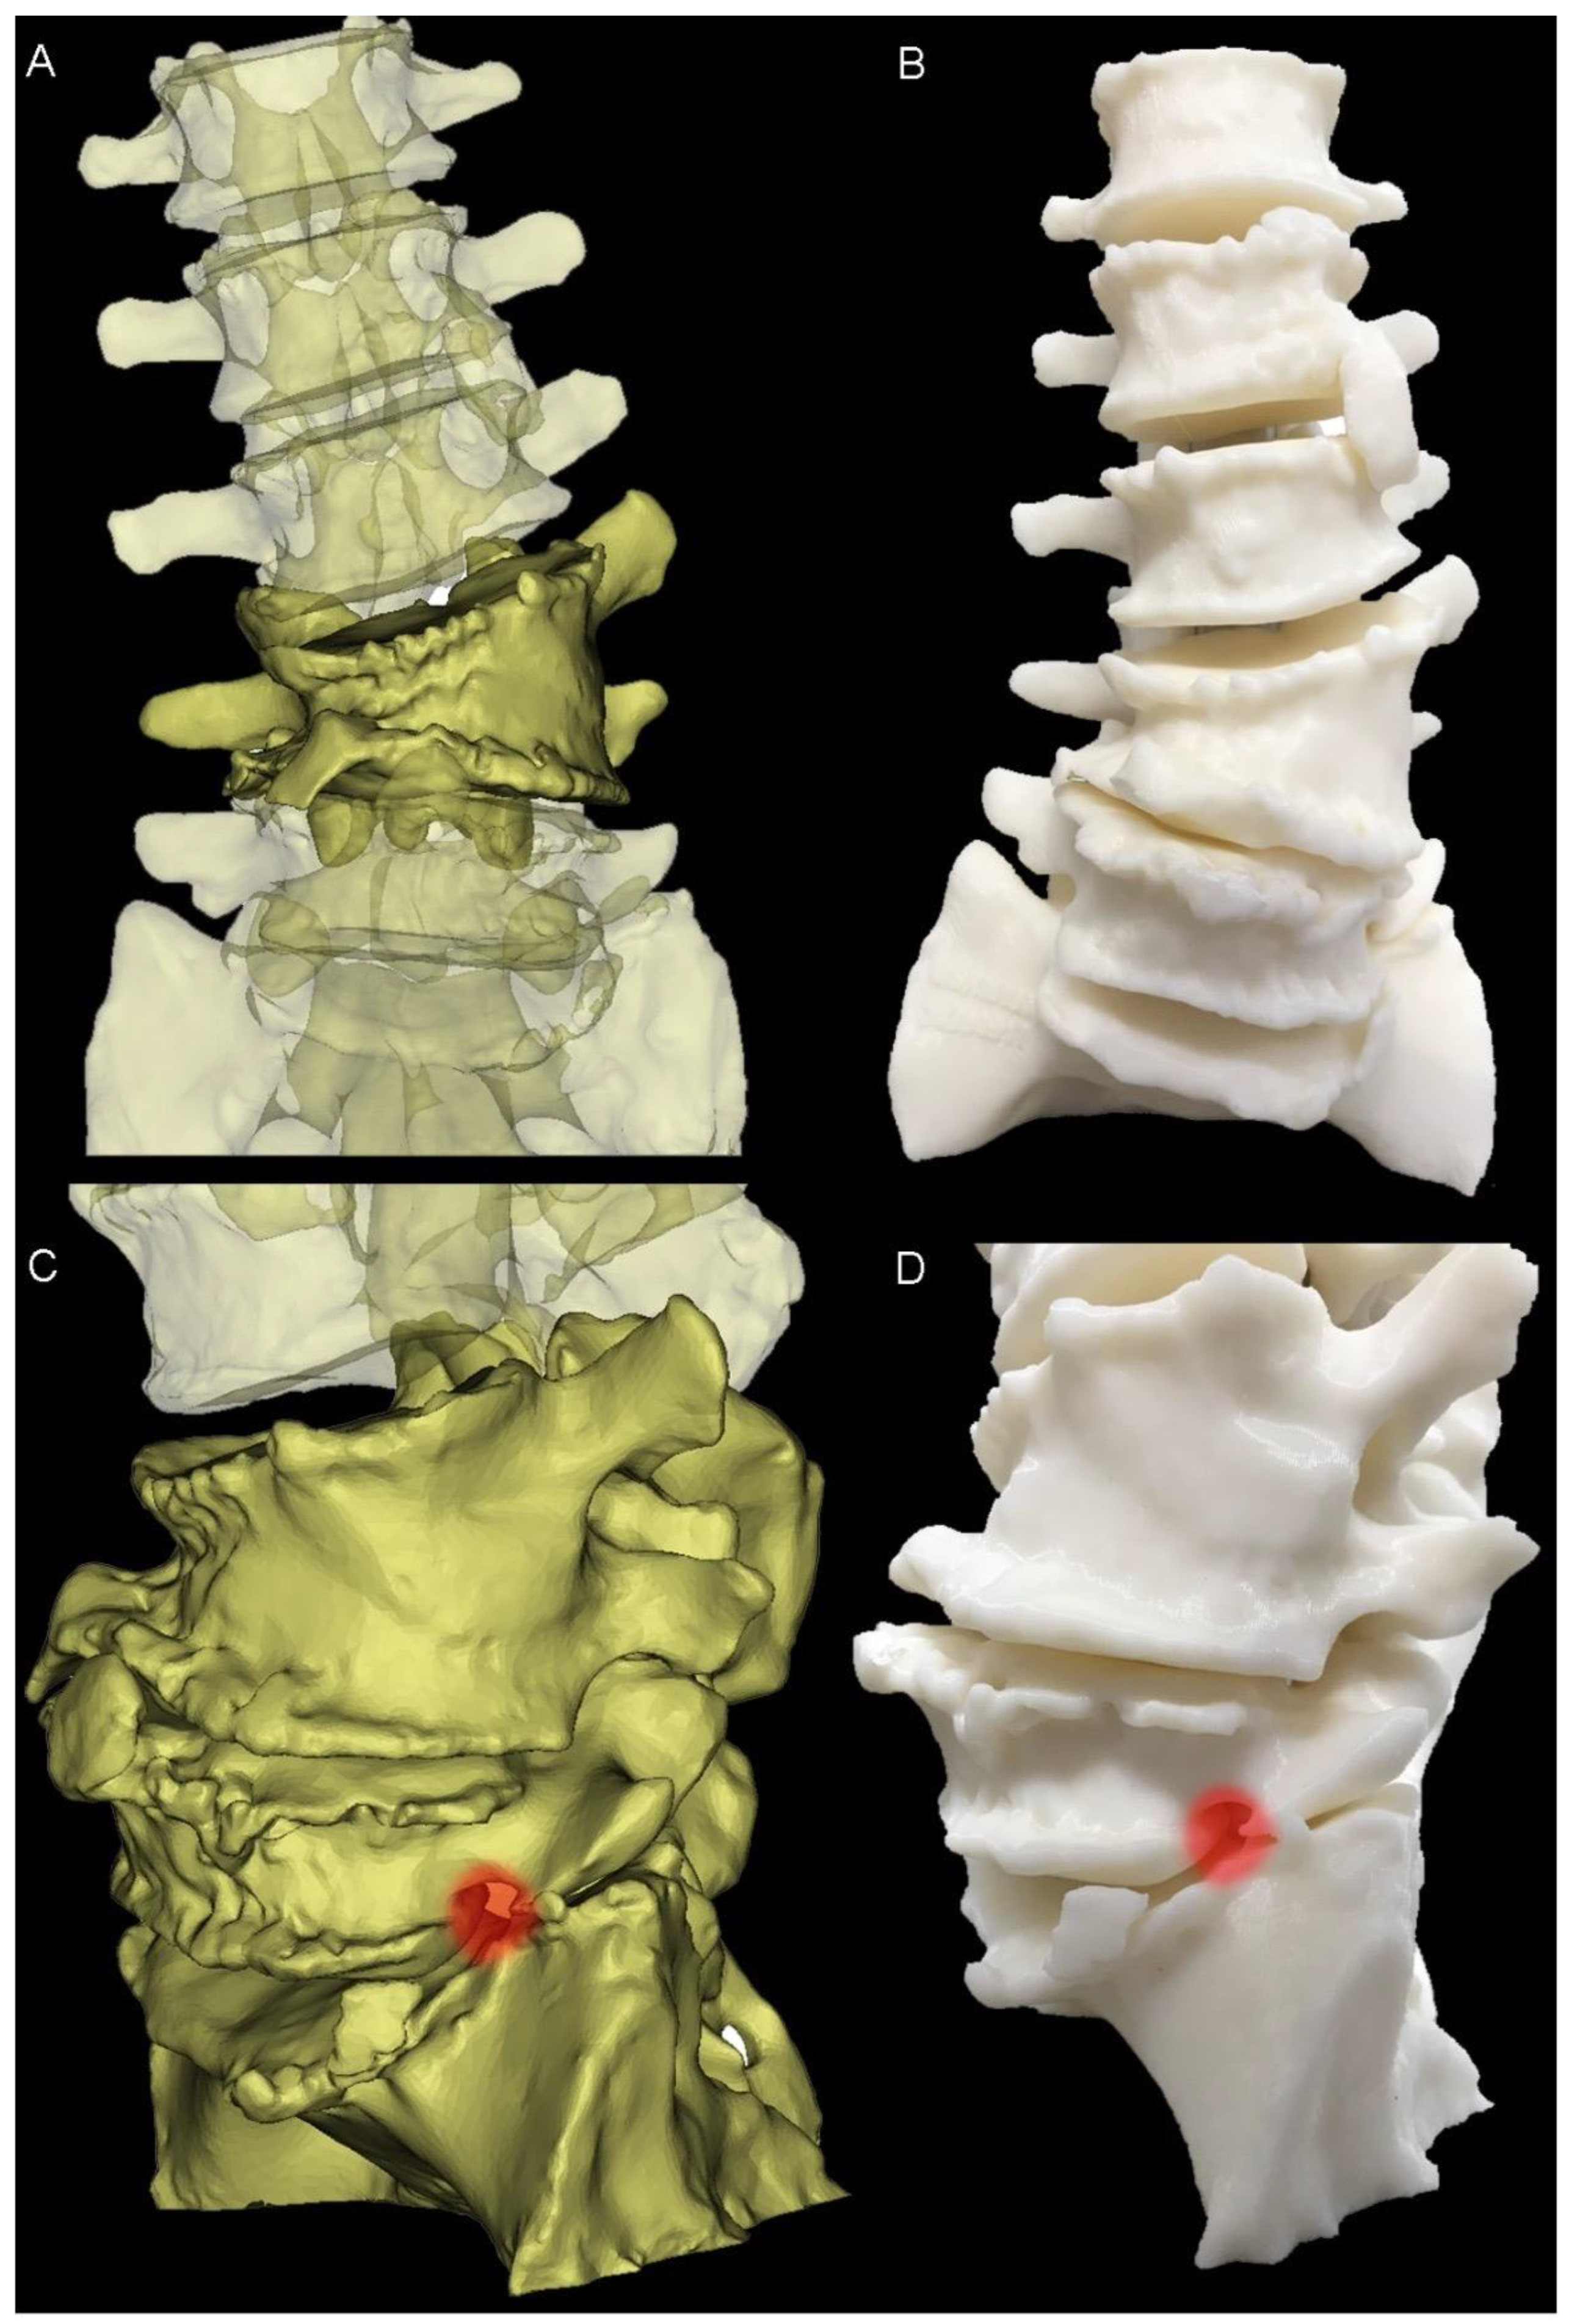

Figure 2.

Three-Dimensional modelling. (A) Anterior view of the preoperative pathological anatomy; hemivertebra is opaque; remainder of the lumbar spine is translucent. (B) Anterior view of the 3D-printed haptic biomodel. (C) Left-hand side view of the virtual model, showing the neuroforaminal stenosis at the L5-S1 level (red highlight). (D) Similar to (C), with the red highlight showing the neuroforaminal stenosis in the 3D-printed biomodel.

2.2. Surgical Planning and Implant Design

The design and manufacture process was performed using 3DMorphic Pty Ltd. (Matraville, Australia) and has been described prior [21]. In brief, this involved thresholding, segmentation, and an initial 3D reconstruction of the patient’s CT using Materialise MIMICs (version 22, Leuven, Belgium). Haptic BioModels [8] of the preoperative pathological anatomy were 3D-printed in acrylonitrile butadiene styrene (ABS) (F170, Stratasys, MN, USA).